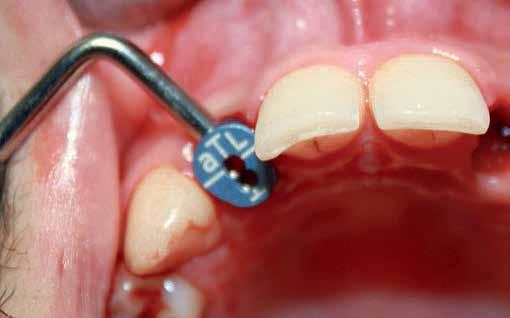

A systemic antibiotic (2g amoxicillin-clavulanic acid, per-orally) was administered to the patients 1 hour prior to the procedure. The patient’s mouth was rinsed with a solution of chlorhexidinedigluconate 0.2% for 2 minutes. After surgical guide printing, the tooth was extracted and the implant placed (IDI implant Implants Di usion International 23/25) following implant placement protocol using a fully guided CAD CAM surgical guide. 14 (fig 3,4,5)

Figure 5: Fully guided implant placement through the surgical guide using spoons. The implant was inserted at the planned position.

Directly after immediate implant placement, a customized healing abutment was fabricated using Cervico kit. The selection was made intraorally using a special handle to place the indicator over the restorable area. (fig 6) Utilize the anatomical shape tab from the same group as per the anterior tooth missing. The anterior suitable stock healing abutment was directly screwed on the implant analog and was fixed at the corresponding well of the silicone mold, and the custom healing abutment was fabricated with nano‐hybrid flowable resin (3M™ Filtek™ Supreme Flowable Composite) (Fig 7,8). Minor selective grinding, finishing, and polishing were made when necessary to achieve a smooth, lustrous tissue contact surface, and screwed to the implant. 15 (Fig 9)